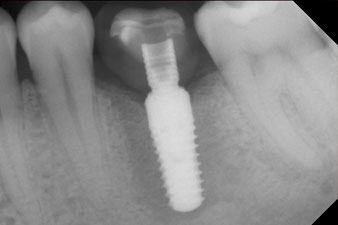

L’implant a été posé comme prévu après élimination complète du tissu de granulation (blueSky, bredent).

Le couple utilisé pour la pose guidée était de 43 Ncm.

En outre, après avoir vissé une tige de mesure (SmartPeg) spécialement conçue pour l'implant, la valeur ISQ a été mesurée à l’aide de la sonde du module W&H Osstell ISQ.

Ce module est fourni en option avec l’Implantmed de W&H et est fixé au moteur d’implantologie (cf. Fig. 11). La valeur ISQ adimensionnelle mesurée immédiatement après l’insertion était de 64 dans l’axe oro-vestibulaire et de 68 dans l’axe mésio-distal (valeur maximale = 100).